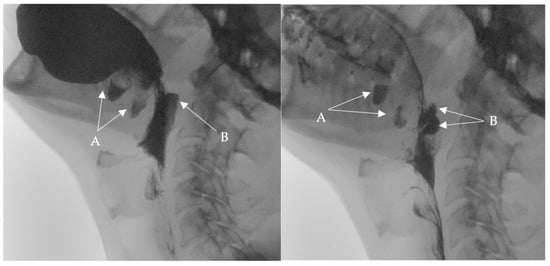

• A videofluoroscopic swallowing study (VFSS) was conducted to assess the oral, pharyngeal, and esophageal stages of swallowing with lateral and anteroposterior views using liquids of thin, thick, and pureed consistencies. The study, conducted by an SLP and a radiologist, showed two posterior inferior oral pouches (buccal diverticula) clearly seen on the floor of the mouth after swallowing. Moreover, two posterior pharyngeal wall pouches (diverticula) in the oropharynx at the level of the second cervical vertebra were visualized (Figure 1 and Figure 2) in addition to regurgitation and flaccid epiglottis. However, no aspiration or penetration was seen during the study.

Figure 2. Selected still images from VFSS, lateral view: simultaneous bolus pooling and contrast residue in (A) two buccal and (B) two pharyngeal diverticula.